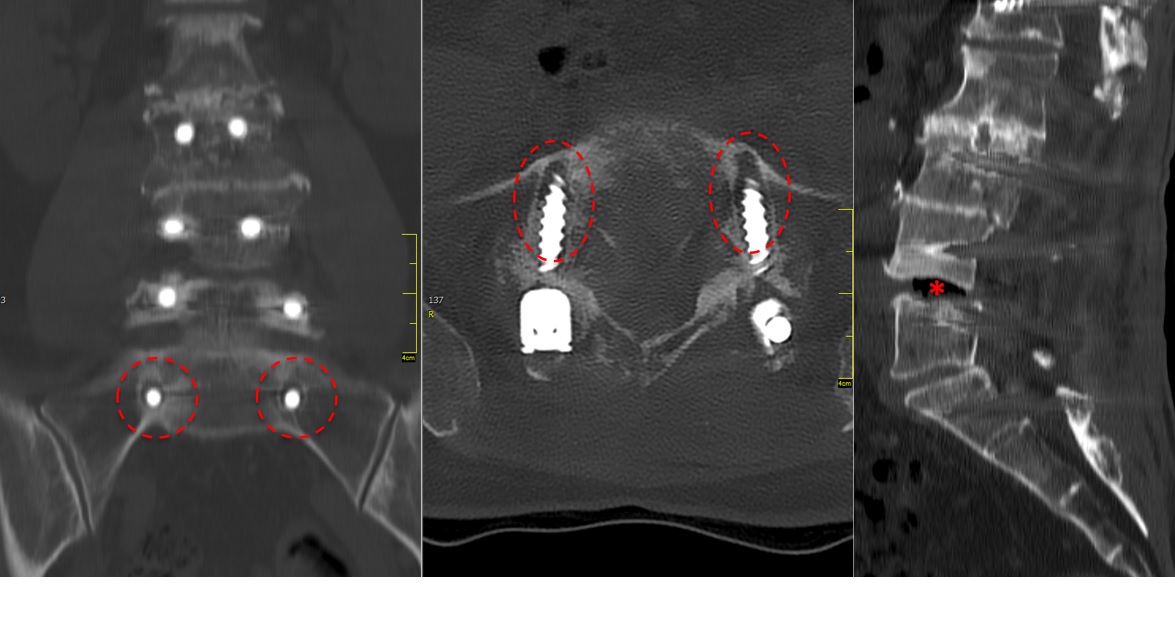

A 75-year-old female patient presented with postoperative back pain. She had been initially operated on eight years earlier with a laminectomy and fusion from L2 to L4. This proved to be successful for a number of years until a second operation was required for secondary back pain and left side leg pain. An extension of the decompression was performed with stabilization and fusion from L1 to S1. The rationale for this operation was unknown and the surgery failed to improve her symptoms.

The problem to be addressed was the patients back pain and left side leg pain, inclusive of some weakness in her left foot. The pain was present upon weight-bearing, with a pain scale of 9. Her discomfort remained at night. The patient was of slim build and was in good general health. She presented with a limp from her left hip and the dorsiflexion of the left foot was weak (M4).

The preoperative standing image of the lumbar spine revealed a flat back with no obvious degeneration of the adjacent segment L1/L2 (Fig 6ab). The implants seemed regularly placed. After wide laminectomy, the spinal canal was open over the whole lumbar spine, illustrated on the MRI scan (Fig 6c).

A CT scan allowed a more detailed assessment (Fig 7). There was an obvious nonunion at L5/S1, with loose screws in the sacrum (red circle). Furthermore, there was instability at L4/L5 as the intervertebral disc presented with an important vacuum phenomenon (asterisk). Foraminal stenosis at L5/S1 (not shown) seemed to be the reason behind the persistent leg pain.

The treatment plan was an anterior height restoration and fusion of L5/S1 and L4/L5. A posterior revision surgery was not considered due to the wide decompression and obvious scar formation. For the correction of level L4/L5, an oblique anterolateral approach (OLIF) was selected due to considerable calcification of the aorta and the iliac vessels. At the L5/S1 level, a straight anterior approach was selected and an additional plate fixation (ATB) was performed.